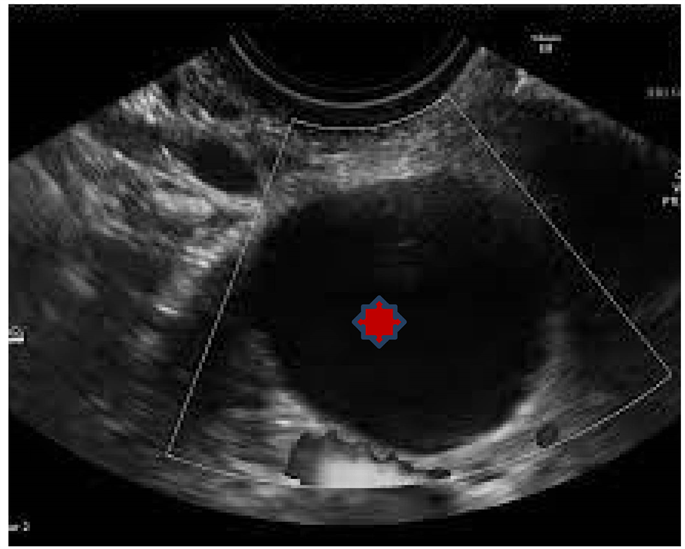

Simple ovarian cyst. Longitudinal image through the pel Openi What Is Avascular Anechoic Cystic Learn about the types, causes, and treatment of benign ovarian cysts, including dysfunctional, corpus luteum, and neoplastic. Determining whether an ovarian tumor is malignant or benign before operation, especially when the tumor has both solid and cystic components, is often difficult. A doctor has provided 1 answer. They can be caused by hormonal changes, pregnancy, infections or other. Learn how. What Is Avascular Anechoic Cystic.

Abdominal ultrasound of the right upper quadrant. A large anechoic What Is Avascular Anechoic Cystic Learn about the common types of ovarian cysts, such. Learn how to use the iota simple rules and adnex algorithm to assess the risk of malignancy of an adnexal lesion on ultrasound. What is anechoic avascular cyst? They can be caused by hormonal changes, pregnancy, infections or other. Determining whether an ovarian tumor is malignant or benign before operation, especially. What Is Avascular Anechoic Cystic.